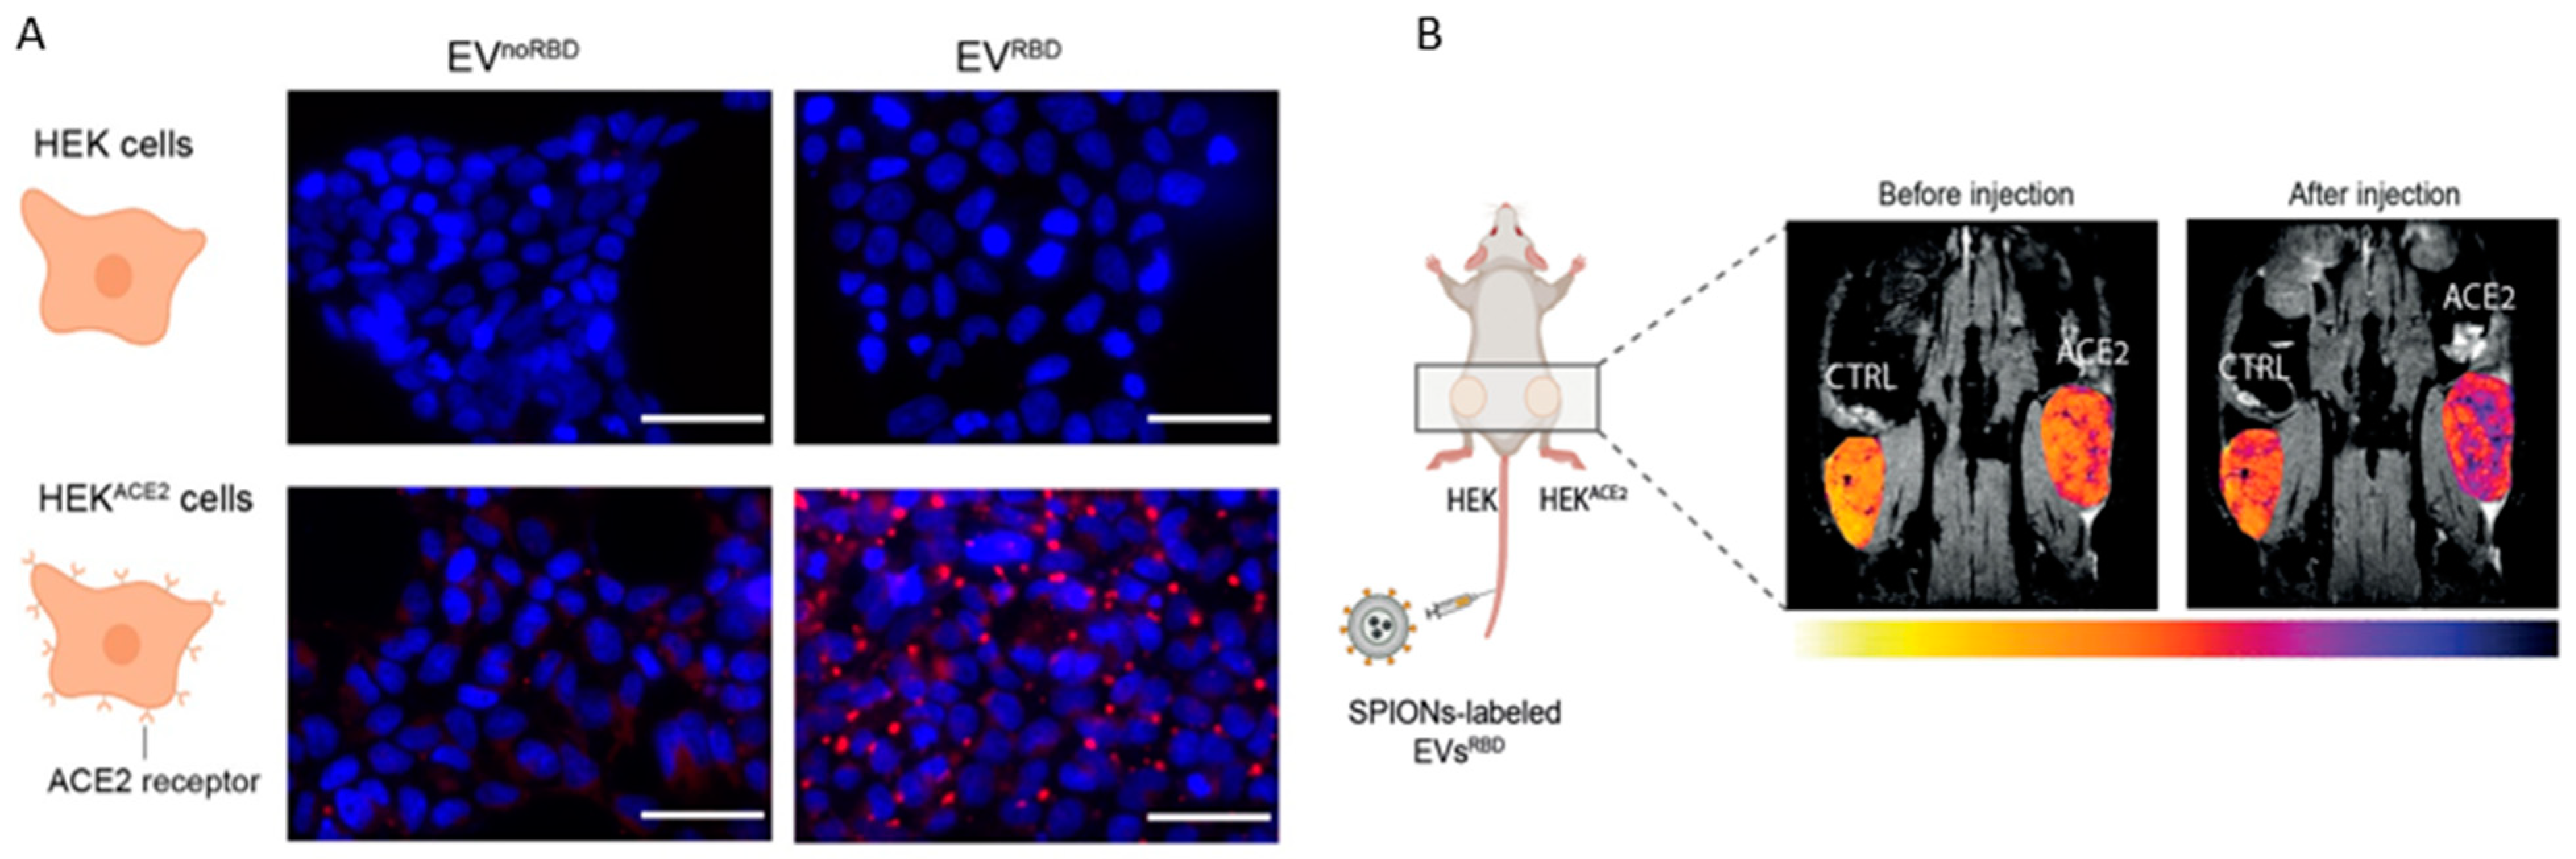

4. MR Imaging

- Galisova, A.; Zahradnik, J.; Allouche-Arnon, H.; Morandi, M.I.; Abou Karam, P.; Fisler, M.; Avinoam, O.; Regev-Rudzki, N.; Schreiber, G.; Bar-Shir, A. Genetically Engineered MRI-Trackable Extracellular Vesicles as SARS-CoV-2 Mimetics for Mapping ACE2 Binding In Vivo. ACS Nano 2022, 16, 12276–12289. [Google Scholar] [CrossRef]